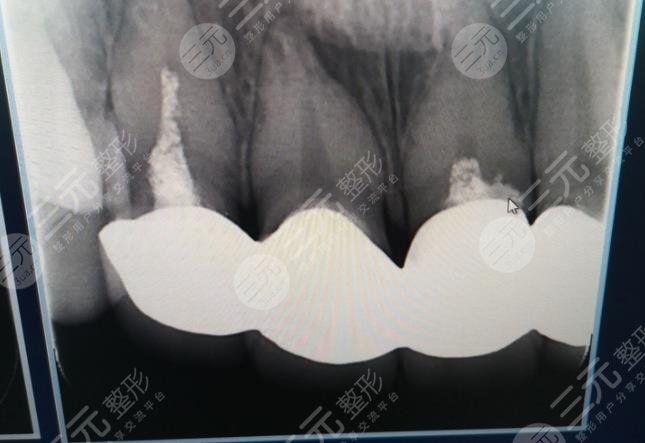

When I went to the hospital for an interview, the doctor asked me to scoop out my teeth on the mold, and a week after that shape, the doctor informed me to go to the hospital for all-ceramic dental plastic surgery, when I first arrived at the hospital, I was actually a little nervous, because I didn't know what would happen, but the doctor and the nurse were very gentle, and explained the whole process to me very carefully, and during the operation, I didn't feel any discomfort, I felt that the whole process was completed in about an hour, and the doctor's technique was very skillful.